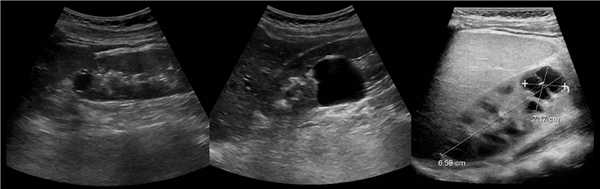

В марте 2002 г. в связи с эпизодом лейкоцитурии лечился у нефролога; при контрольном УЗИ впервые диагностированы изменения в мочевом пузыре и паравезикально слева. При повторном УЗИ выявлено (рис. 1а): правая почка увеличена в размерах (длина 12,7см; толщина паренхимы 1,6 см); чашечно-лоханочная система не расширена. Левая почка отсутствует. Стенки мочевого пузыря не изменены; в просвете слева определяется округлое образование 3,5 x 4,6 x 5,0 см с неоднородным содержимым (объем около 40 мл). Заключение: аплазия левой почки; уретероцеле слева.

а) Эхограмма.

б) Компьютерная томограмма.

в) Схема КТ.

Компьютерная томография (КТ): в проекции устья левого мочеточника и на фоне мочевого пузыря слева определяется дополнительная тень 3,1 x 4,0 x 4,0 см с четкими контурами и плотной стенкой. Мочеточник выше устья расширен до 1 см. Заключение: КТ-картина уретероцеле слева, уретерэктазия слева (рис. 1 б, в).